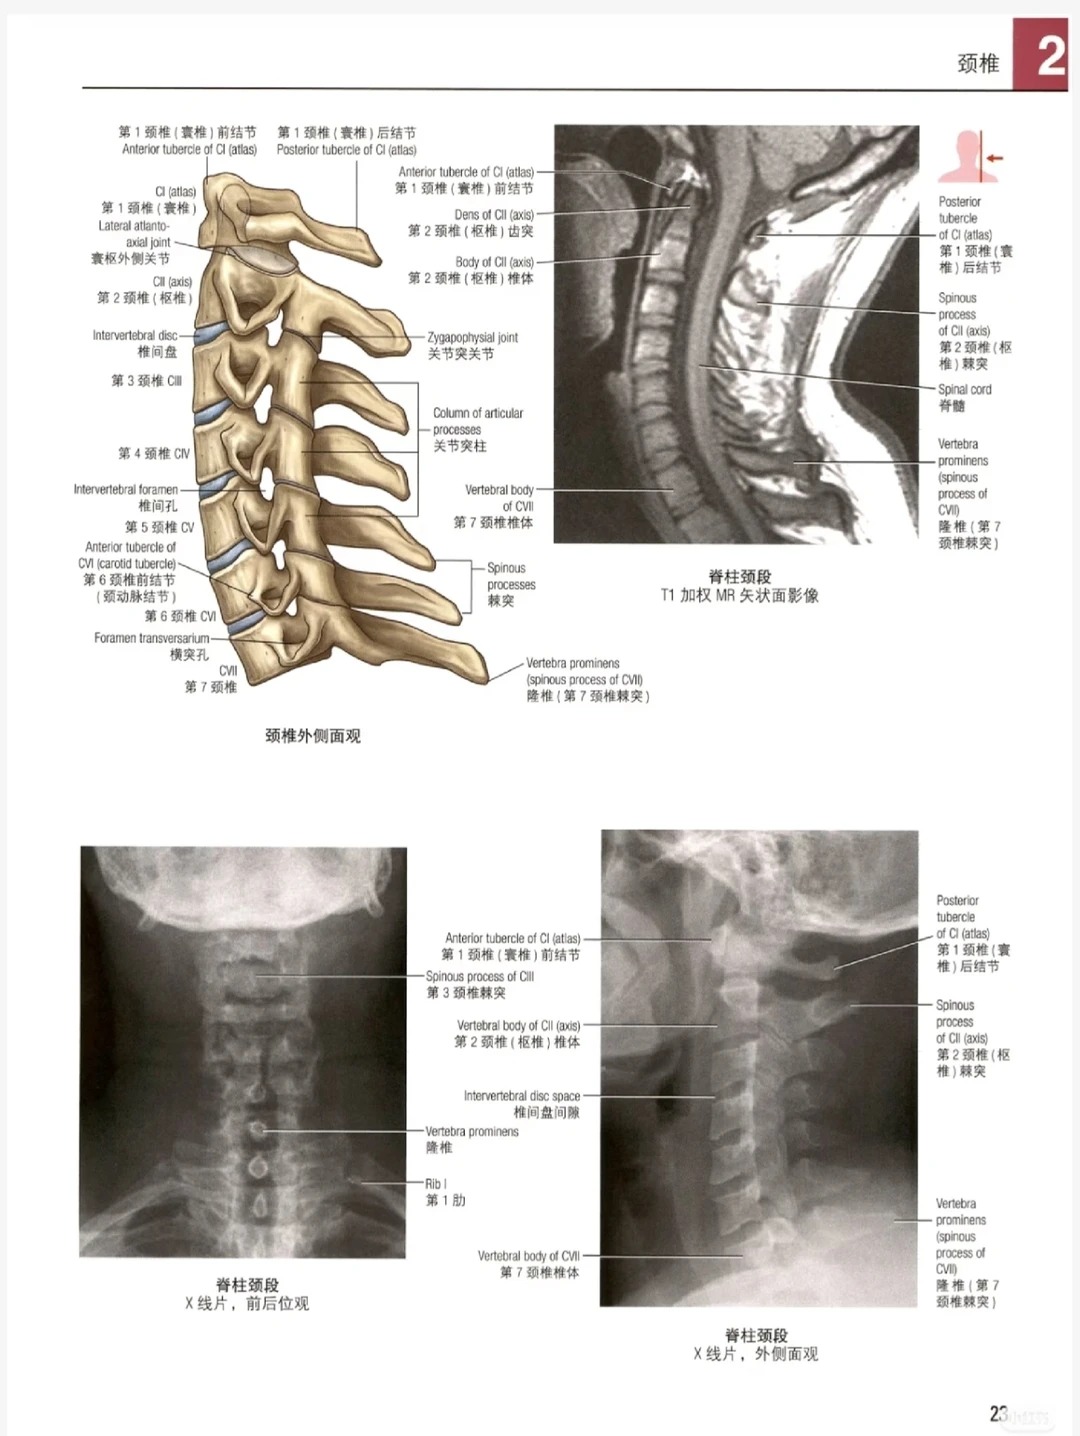

直到挖到《格氏解剖学图谱》第3版高清中英文版,直接救大命、直接封神yyds,没有之一、没有之一、没有之一!第3版重磅更新,每一处升级都精准戳中我们的痛点,彻底告别解剖难学的困境!超高清全彩插图,细节拉满,每一页都是视觉盛宴,骨骼、肌肉、神经、血管层次分明、一目了然,再也不用眯着眼睛看模糊图谱,记起来更轻松;新增临床影像学对照,衔接临床实操,学完就能用,解决理论与临床脱节的问题,临床实操时再也不用无从下手;解剖结构标注更清晰直观,关键结构重点标注,告别标注混乱、分不清的困扰,一眼就能看清核心结构;系统解剖+局部解剖双重视角,全方位掌握解剖知识,不用东拼西凑找资料,搭建系统的解剖知识体系;高清中英文双版本,适配不同学习需求,医学生、考研党、临床工作者都能精准适配,想对照原版学习、备战考研都能满足;内容权威精准,经过专业修订,贴合医学学习和临床实操需求,不管是学习、考试,还是临床实操,都能直接参考,入手后直接开挂,彻底摆脱内耗,再也不用内耗到emo、不用熬夜瞎找资料、不用为解剖难题发愁,轻松掌握解剖知识、顺利通过考试、精准开展临床实操,谁入谁赚、谁入谁赢,不入手真的亏麻!

具体宝藏解剖图谱亮点,家人们速码,不看亏麻👇 建议直接截图保存,别偷懒、别错过,亏麻别找我,我已经反复提醒你啦,主打一个良心种草,不玩套路、不割韭菜,冲就完事儿!

✅ 全网难寻:《格氏解剖学图谱》第3版高清中英文版,第3版重磅更新,超高清全彩插图、临床影像对照,专为医学相关人群量身打造,错过再等N年,不入手亏麻,谁不入手谁是大冤种、谁不入手谁亏麻到哭死!